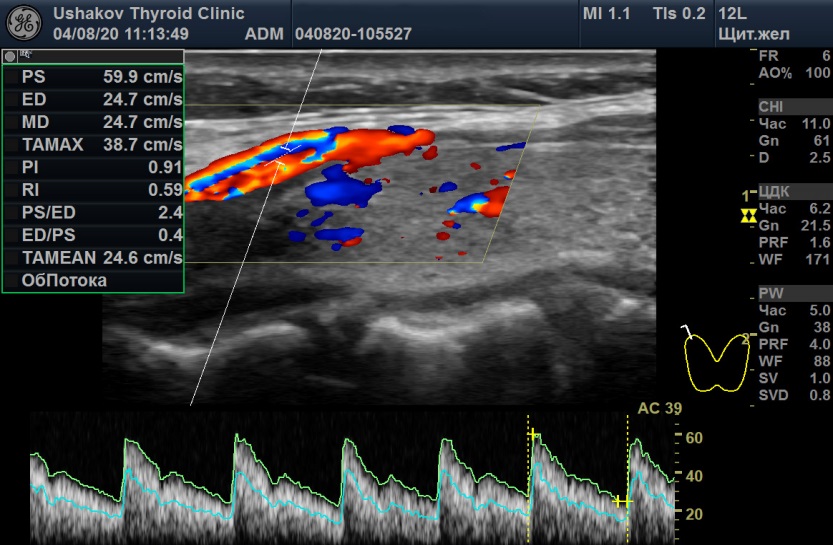

При анализе крови 31.07.20 ТТГ 11,5мМЕ/л [0,4-4,0], Т4св. 9,5 пмоль/л [9,0-19,1], Т3св. 5,3 [2,63-5,7], Т4общ. 74,5 нмоль/л [66,6-150,8], АТ-ТПО 1302 МЕ/мл [<5,6], АТ-ТГ 277 [<10]. Величина антител к рецепторам ТТГ не определялась в связи с гипотиреозом. УЗИ щитовидной железы 04.08.20 показало объем 9,6 мл (6+3,6), признаки умеренного отёка стромы, малые явления мелко-дольковой деструкции, малую лимфоцитарную инфильтрацию, малое усиление кровотока двух долей и ПССК верхних щитовидных артерий 59,9 см/с справа и 40,6 см/с слева (

рис. 6 и 7).

Рисунок 7 Максимальная пиковая скорость крови в верхних правой и левой артериях щитовидной железы пациентки С., 22 года. А – 04.08.20 в правой артерии ПССК 59,9 см/с, Б – 11.09.20 в правой артерии ПССК 105 см/с.

Избыточная нервная стимуляция ЩЖ отразилась также на изменении ПССК при допплерографии (

рис. 7). Максимальная ПССК в правой артерии увеличилась с 59,9 см/с (04.08.20)

до 105 см/с (11.09.20), а в левой – с 40,4 см/с (04.08.20), до 62 см/с (11.09.20). Эти большие значения ПССК (особенно 105 см/с) характерны для гипертиреоза и указывают на проводниковую нервную стимуляцию тиреоидной сосудистой сети вместе с усилением напряжения ткани щитовидной железы.